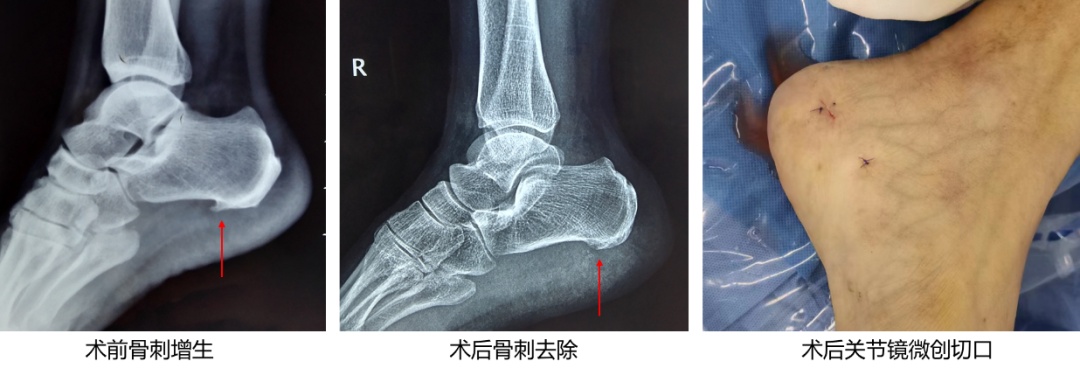

在正规保守治疗无效后,手术治疗是治疗慢性足跟疼痛的最后方法。传统手术包括开放手术切除骨刺或周围神经松解、小针刀松解跖腱膜等,但开放手术创伤较大、小针刀定位困难等缺点困扰着临床医生。

目前,微创治疗愈发被患者所接受,关节镜下跖腱膜松解术、骨刺切除术等技术越来越成熟,且应用逐布广泛,将来有可能成为慢性跟痛症的首选手术方案,且符合现代微创和快速康复理念。此外,超声引导下部分筋膜切开术、自体足部脂肪移植等术式也在推广应用。